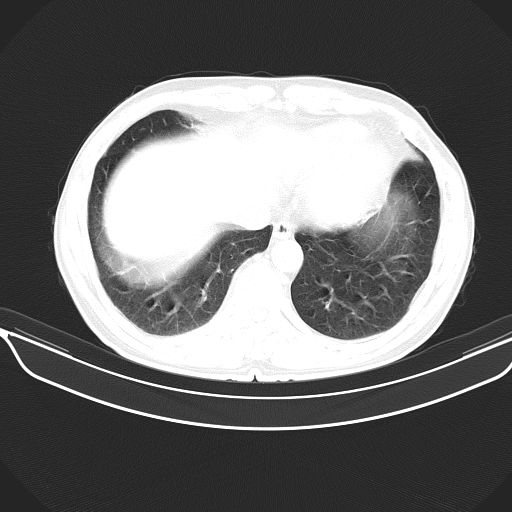

以下是引用shuiyuan在2010-3-1 10:45:00的发言:[br]考虑左肺上叶中心型肺癌伴阻塞型炎症,邻近胸膜受侵。

以下是引用心路寻觅在2010-3-1 10:23:00的发言:[br]1、考虑左肺上叶周围型肺癌[br]2、右上肺陈旧性病灶。[br][br][本贴已被 心路寻觅 于 2010-3-1 10:40:18 修改过]